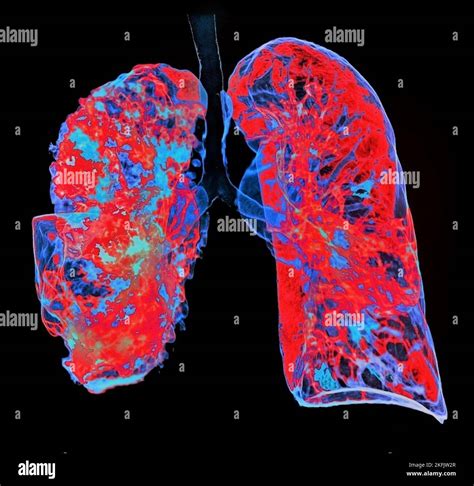

When a respiratory infection lingers or becomes severe, healthcare providers often look for more detailed imaging than a standard chest X-ray can provide. This is where a Pneumonia CT Scan becomes a critical diagnostic tool. Unlike a traditional X-ray, which produces a two-dimensional image, a computed tomography (CT) scan creates detailed, cross-sectional views of the lungs. This allows doctors to visualize the extent of inflammation, identify complications like abscesses or pleural effusions, and accurately differentiate pneumonia from other lung conditions. Understanding when and why this imaging procedure is necessary can help patients better navigate their diagnostic journey.

While a physical examination and medical history are the first steps in diagnosing pneumonia, imaging is required to confirm the presence and severity of the infection. A Pneumonia CT Scan is not always the first choice, but it becomes essential in specific clinical scenarios. By providing high-resolution images, it helps physicians make informed treatment decisions.

Choosing the right imaging modality is crucial for accurate diagnosis. While the Pneumonia CT Scan is superior in detail, other methods have their place in clinical practice.

Pneumonia CT Scan Detailed, 3D cross-sectional views Complex cases, complication assessment, and differential diagnosis.